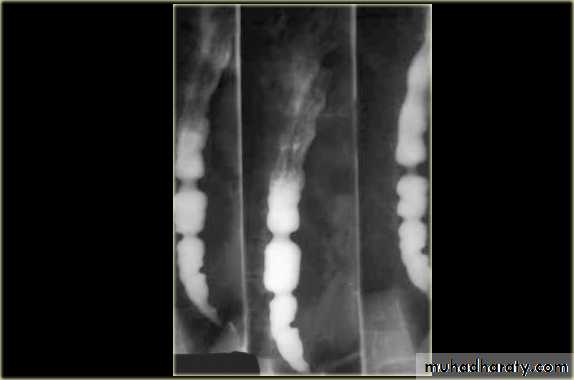

Investigations Chest X-ray; widening of the mediastinum, aspiration pneumonia.A barium swallow; tapered narrowing of the lower esophagus, esophageal body is dilated, aperistaltic and food-filled.Endoscopy; must always be carried out, carcinoma of the cardia can mimic the presentation and radiological and manometric features of achalasia ('pseudo-achalasia').Manometry; confirms the high-pressure, non-relaxing lower esophageal sphincter with poor contractility of the esophageal body.

Investigations Endoscopy; The investigation of choice, with cytology and biopsy.Barium swallow ; site and length of the stricture .Thoracic and abdominal CT Endoscopic ultrasound (EUS)